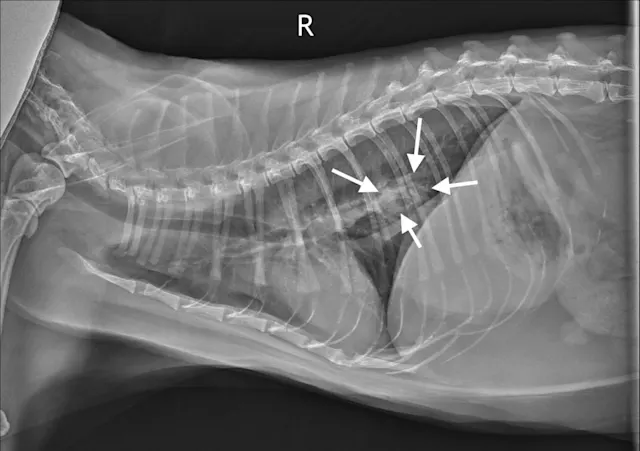

Figure 1A

Canine lung tumor

In these 3-view thoracic radiographs of an 8-year-old neutered male boxer with a lung tumor, a large soft tissue mass visibly extends to the lung lobe margins, nearly causing complete consolidation of the right middle lung lobe. Several closely spaced air bronchograms at the caudal margin of the mass are consistent with atelectasis caused by the expansile nature of the mass (Figure 1A; arrows). The apparent right mediastinal shift (ie, shifting of the cardiac silhouette to the right) in the ventrodorsal view (Figure 1C) is, at least in part, due to a moderate degree of patient rotation.

This patient underwent a right intercostal thoracotomy and lung lobectomy for tumor resection. On exposure of the thoracic cavity during surgery, it was found that the tumor was in contact with the right side of the heart, and, accordingly, occasional ventricular arrhythmias (ie, 3-4 per minute) were noted. A narrowly excised low-grade pulmonary carcinoma was confirmed via histopathology.